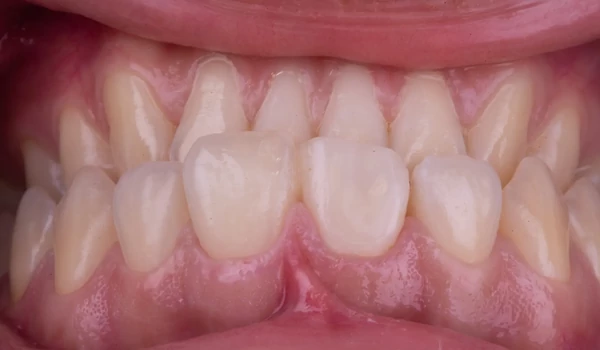

3. Preparáció és digitális lenyomatA végleges restaurációhoz ¾-koronás preparációt végeztek, majd intraorális szkennert használtak lenyomatvételre. Ezt követően ideiglenes koronát készítettek, s árnyalatfotókat is rögzítettek kuraraynoritake.eu. |

14. ábra. Ideiglenes restauráció a helyén. |